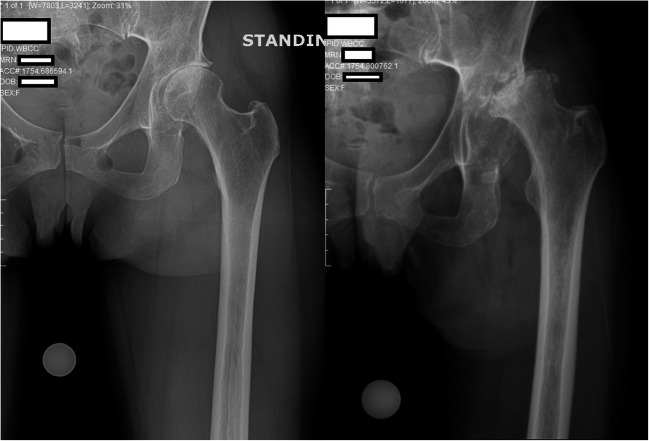

The patient is a 76-year-old female who suffered a subcapital femoral neck fracture at an outside institution in November of 2019, at which time she underwent closed reduction and percutaneous pinning. However, she later presented to our arthroplasty service during the COVID-19 pandemic, complaining of rapidly worsening left-sided hip pain with the inability to bear weight. Per the patient’s daughter, her clinical condition had deteriorated particularly over the previous 2 weeks, with multiple episodes of stumbling and tripping due to the worsening hip pain and inability to bear weight on the left side. The patient stated that night-time was particularly dangerous for her, as she had extreme difficulty with toileting due to the pain and dysfunction in her left hip, and was fearful that she may injure herself in a fall. By the time of presentation, the patient reported she was essentially confined to bed due to her deteriorating clinical status. Plain radiographs demonstrated the previous percutaneous fixation of the patient’s subcapital femoral neck fracture with three cannulated screws. However, the fracture construct was seen to have collapsed into nonunion, with a persistently visible fracture line and shortening of the femoral neck, with resulting partial backing-out of the screws laterally (Fig. 3).

Fig. 3.

Anteroposterior pelvis radiograph demonstrating percutaneous cannulated screw fixation of a valgus-impacted femoral neck fracture. The fracture construct is seen to have collapsed into nonunion, with a persistently visible fracture line and shortening of the femoral neck, with resulting partial backing-out of the screws laterally

The case was referred to a multidisciplinary peer-review panel at our institution. The unanimous decision was made to proceed urgently with conversion THA. Other than advanced age, the patient had no past medical history that would put her at additional risk in the setting of COVID-19, and she was felt to be at significant risk for future falls, injury, and potentially greater morbidity if the surgery was to be delayed. Her clinical status was essentially comparable to a hip fracture patient. She subsequently underwent uncomplication conversion THA and was discharged home on post-operative day two.